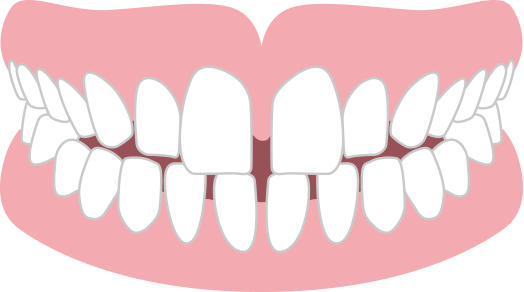

ガタガタ 叢生

あごと歯、それぞれの大きさのバランスが悪く、歯列にきれいにならびきらずに歯が重なったりねじれたりしている状態。

見た目に問題がある他、歯磨きがしづらく、虫歯や歯周病になりやすいです。